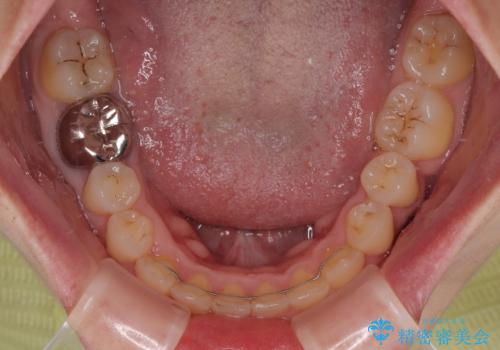

前歯のクラウンは変色が顕著なため、矯正治療後にオールセラミッククラウンによる補綴治療を行うこととしました。

前歯のクラウンは、歯肉内深くに削り込まれており、歯肉の炎症が継続していたため、矯正治療後に歯周外科処置を行い、歯肉の腫れを改善させました。